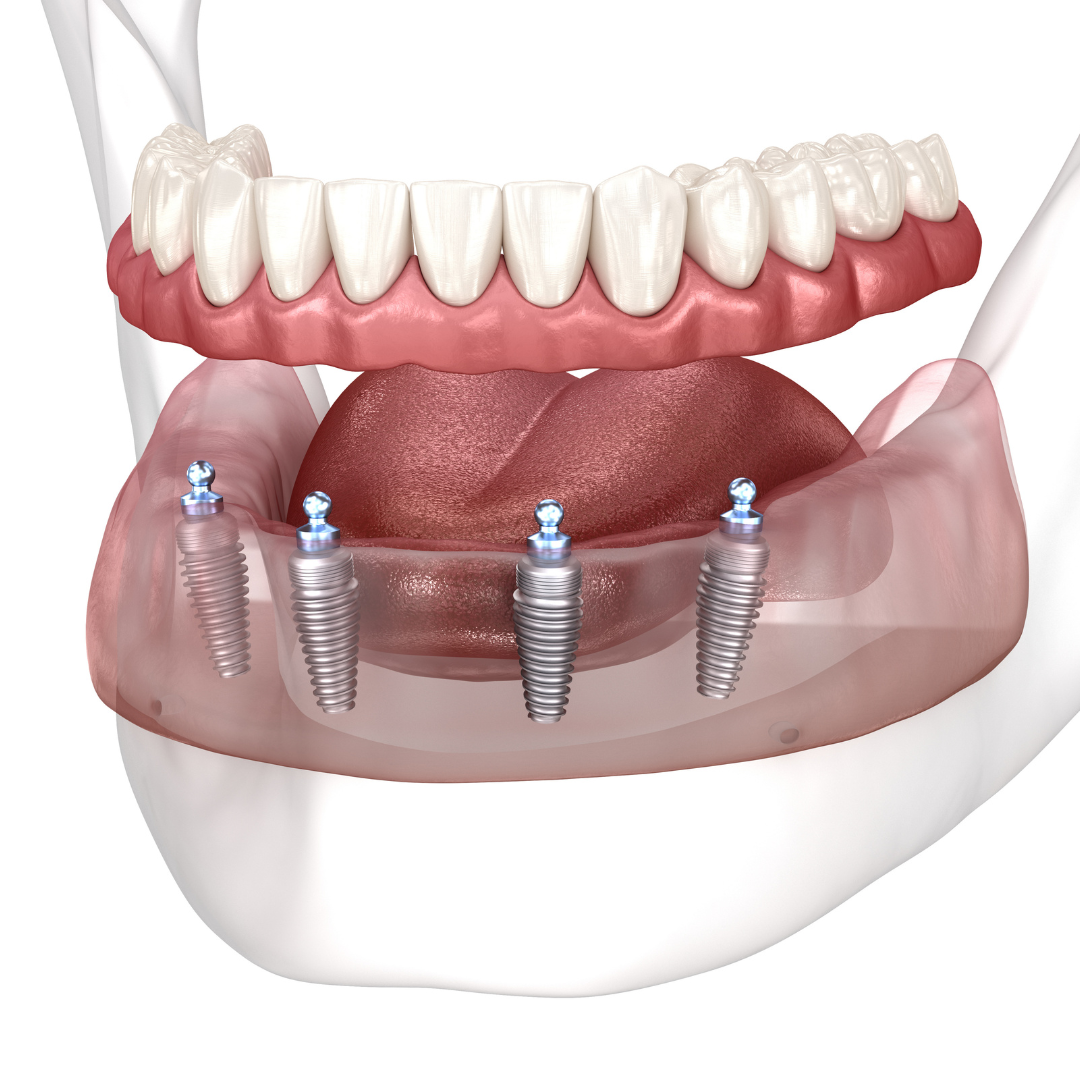

Includes everything from start to finish. No hidden fees.

Includes surgical placement of 2 to 4 implants.

Includes abutments

Includes healing denture.

Includes final snap-on implant denture.

Patients no longer have to deal with low-quality temporary solutions like dentures, bridges, or partials. Dental implants are the new leading standard in tooth replacement options. They act and feel just like real teeth with an average lifespan of 20+ years.

So, how do they work?

Every single dental implant consists of three parts - the implant, the abutment, & the crown. The implant is made of medical grade titanium. This part is surgically placed into the patient’s jaw bone and left to heal for 4-6 months afterwards.

This implant piece acts as the foundation for the rest of the tooth. Once the bone around the site has healed, the abutment and crown are placed on top of the implant. The end result is a beautiful, natural-looking new tooth!